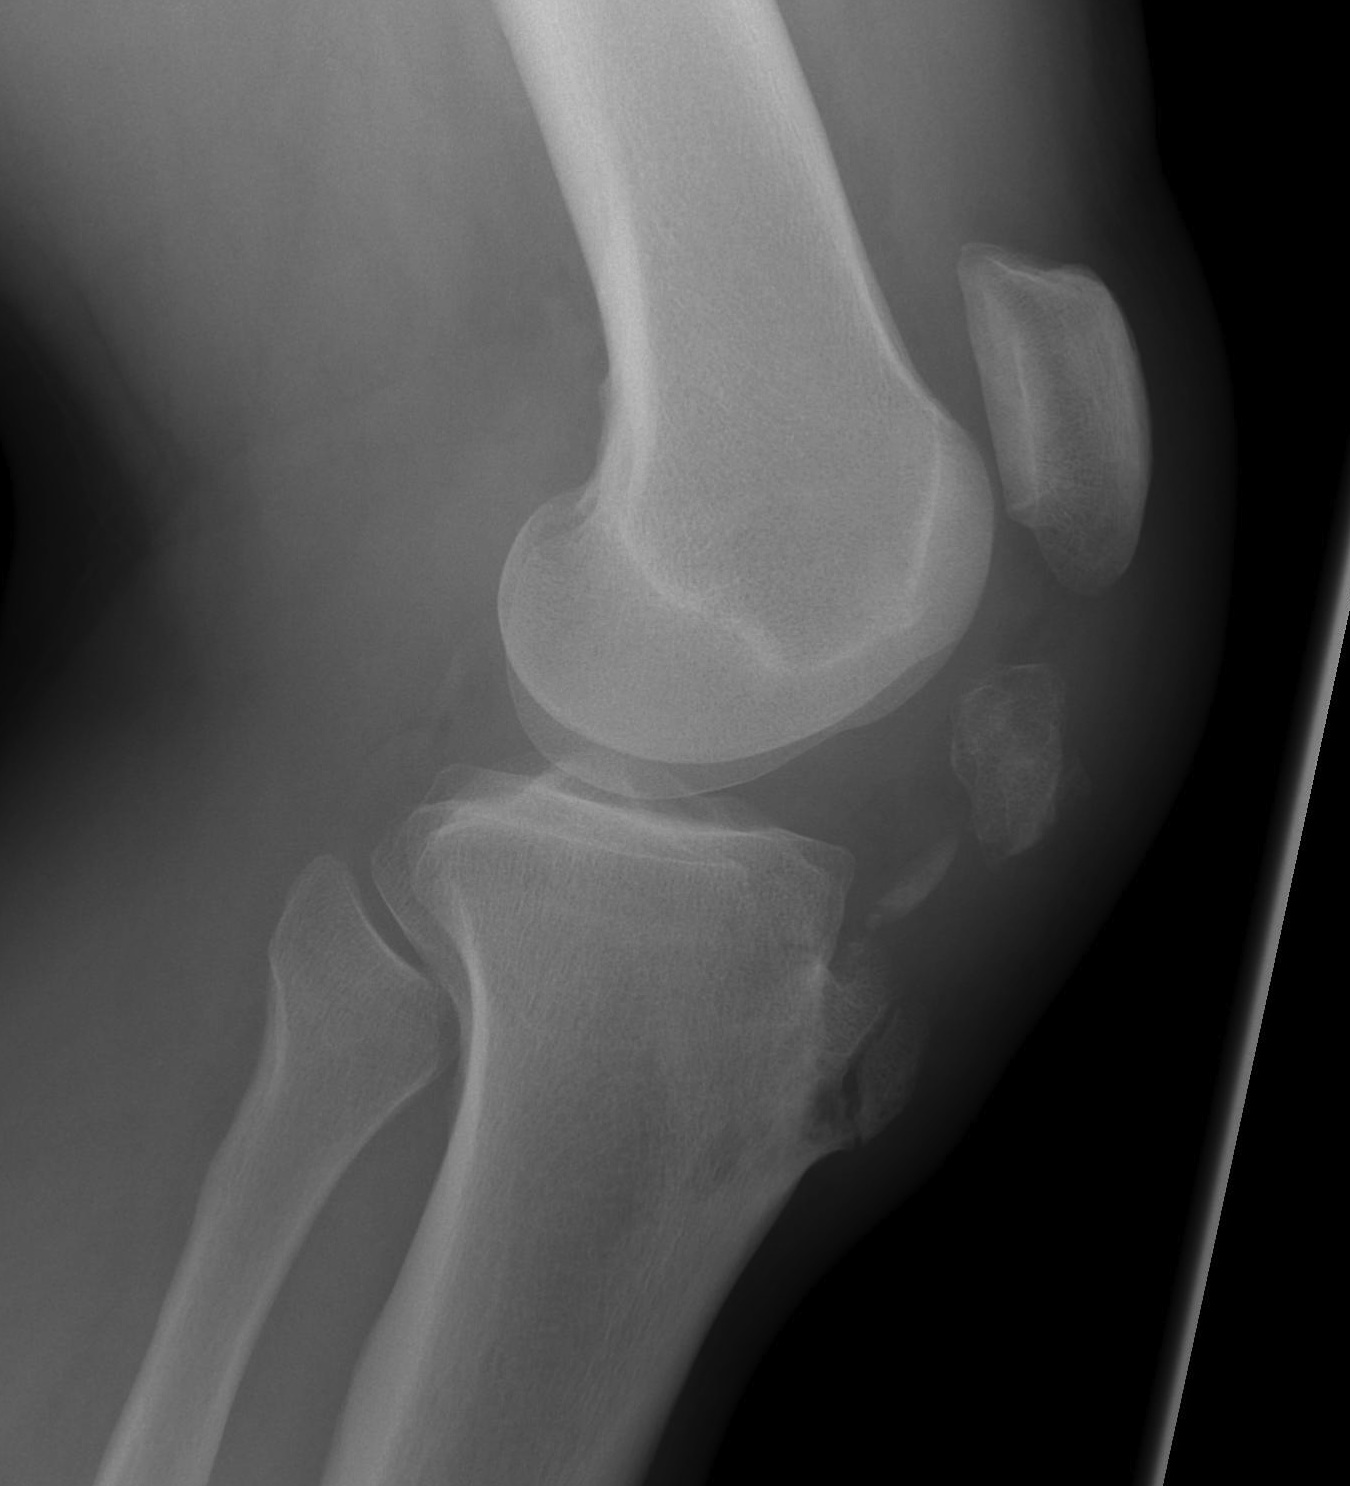

Xray

Patella alta / high riding patella

Distal Pole Patella Fracture